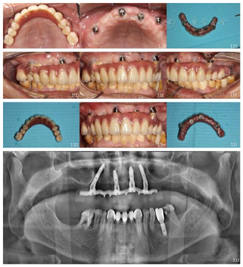

随访及转归:上颌种植固定义齿修复5年,每年定期复查,修复体完整稳固,无机械并发症发生;种植体周围软组织健康稳定(图11A~I,图12A~I,图14)。

随访X线检查示4颗种植体周围骨结合良好(图10,图11J,图12J,图13,图15)。

面像;B:复合基台情况;C:义齿组织面存留食物软垢;D:右侧咬合像;E:正面咬合像;F:左侧咬合像;G:清洁后义齿

面像;H:重新戴入后正面咬合像;I:清洁后义齿组织面像;J:曲面体层片

面像;H:复合基台情况;I:义齿组织面存留食物软垢;J:根尖片

All-on-4®即刻种植即刻负重后口腔卫生与维护十分重要。因此无论是临时固定义齿还是终义齿,均将义齿组织面与牙龈间设计为"端对端"的凸面接触(图7B),此种接触关系更有利于患者进行口腔卫生的维护,减少食物残渣滞留,避免种植体周围软组织炎症发生[20]。按照种植体支持式全牙列固定义齿复诊与维护指南[21]对患者进行每3个月随访,口腔卫生指导包括牙间隙刷、冲牙器、牙线及超级牙线的使用指导,菌斑检查与控制(图12D、E、F、H、I),嘱咐患者戒烟或减少吸烟量,文献证明良好的菌斑控制可以有效地预防种植体周黏膜炎的发生[22]。

随访维护期内发现患者右侧下颌第二前磨牙与第一磨牙牙周炎症较5年前进一步发展,影像学检查示牙槽骨吸收至根尖(图15),符合拔牙指征[7,8],患者知情同意后拔除,后期及时修复,保持全牙列的咬合平衡。